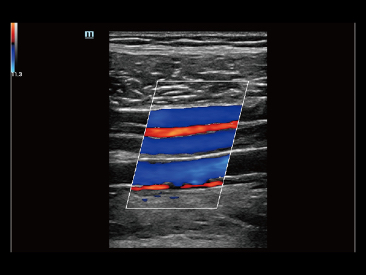

Sejak didirikan, Mindray terus mencari cara baru untuk meningkatkan keandalan diagnostik. Didukung Teknologi ZONE Sonography? terkini, platform ZST+ baru Resona 7 meningkatkan kualitas gambar ultrasound melalui pengambilan zona dan pemrosesan data saluran.

Selain kualitas gambar premium, Resona 7 juga meningkatkan kemampuan penelitian klinis dengan V Flow revolusioner untuk evaluasi hemodinamika vaskular, serta pengambilan penampang tercanggih dari rangkaian data 3D untuk diagnosis CNS pada janin. Kombinasi pengoperasian multisentuh berbasis gerakan yang paling intuitif dengan semua fitur klinis penting membuat Resona 7 menjadi gebrakan baru dalam inovasi ultrasound.